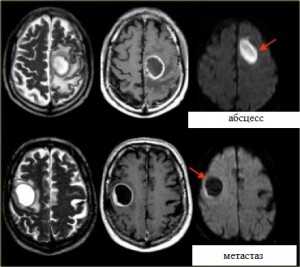

Яркие очаги на диффузионное-взвешенных МРТ изображениях характерны для абсцессов, эпидермоидных кист, и острого инсульта. Опухоли имеют низкий сигнал на ДВИ МРТ головного мозга.

МРТ головного мозга. Аксиальные Т2-взвешенные МРТ, Т1-взвешенные МРТ с контрастировавшем и ДВИ МРТ.